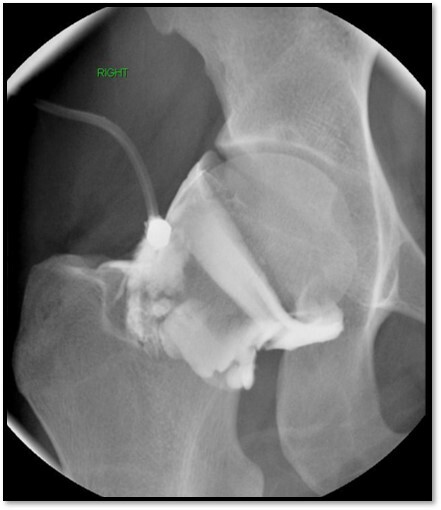

Infected arthroplasty

What is this showing here?

A

Antibiotic leads